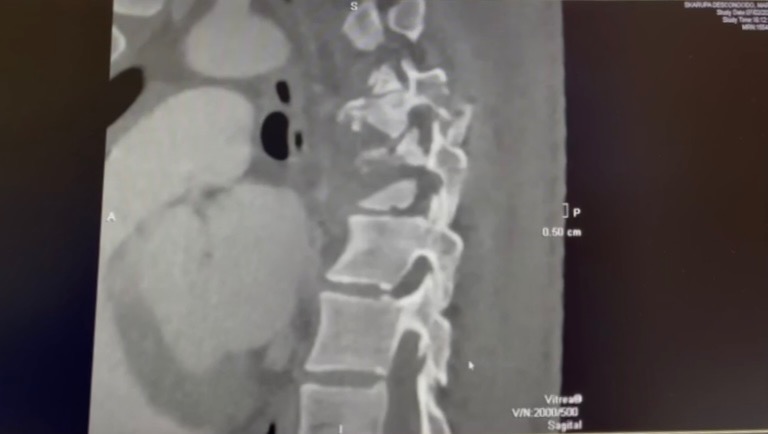

Mein Bruder Mark (26, Student) hatte letzte Woche leider einen schweren Fahrradunfall, bei welchem unter anderem einige Wirbel gebrochen und sein Rückenmark schwer beschädigt wurde. Seitdem ist er Querschnittsgelähmt und hat das Gefühl ab Brusthöhe verloren. Aktuell liegt er in der orthopädischen Klinik in Heidelberg.

Unfortunately, my brother Mark (26, student) had a very serious bike accident last week. Due to the accident a few vertebrae were broken, and his spinal cord was severely damaged. Since then he has been paraplegic and has lost all feeling from chest level downwards. He is currently being treated at the orthopedic clinic in Heidelberg, Germany.

Por desgracia, mi hermano Mark (26, estudiante) tuvo un accidente de bicicleta muy grave hace una semana, en el que se rompió algunas vértebras, y su médula espinal quedó gravemente dañada. Desde esto, está parapléjico y ha perdido la sensibilidad a partir del pecho. Actualmente se encuentra en la clínica ortopédica de Heidelberg, Alemania.